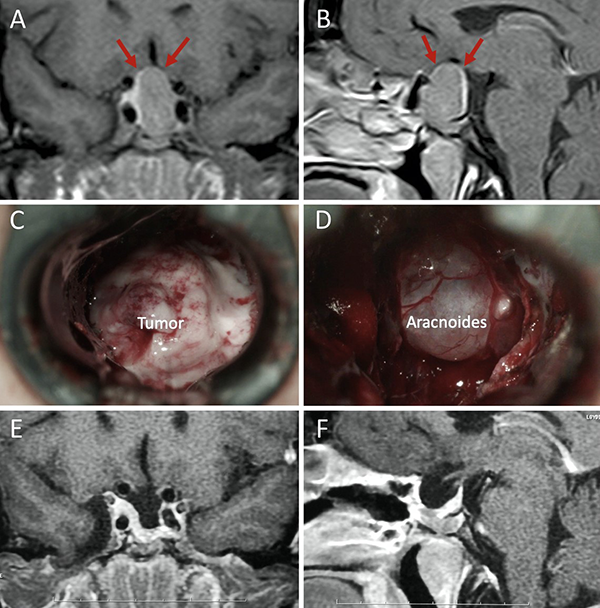

Una clasificación clásica de los adenomas es según su tamaño. Se los clasifica en microadenoma <10 mm (fig. 2), macroadenoma >10 mm (fig. 3), y adenoma gigante > 30 mm (fig. 4). Esta clasificación es importante ya que los índices de remisión están ligados al tamaño del adenoma y también su recidiva.12

Figura 4: Adenoma gigante. A-B: RM preoperatoria; C-D: RM postoperatoria.

El techo de la fosa pituitaria está constituido en condiciones normales por un máximo de 2 estructuras: duramadre (diafragma selar) y aracnoides.65,66 En condiciones patológicas, cuando existe un adenoma hipofisario, éste empuja hacia arriba a la glándula. De este modo, la interfase entre el tumor y el LCR se encuentra constituida por un máximo de 3 elementos: glándula, duramadre y aracnoides. Cabe destacar que la aracnoides es el único elemento constante. A los elementos que constituyen esta interfase el equipo de Tucumán los denominó “barrera selar”.11,60

Existen 3 subtipos de barrera selar según los hallazgos intraoperatorios, luego de resecar el tumor:

Un factor interesante de este novedoso concepto es que el tipo de barrera puede evidenciarse en la RM preoperatoria. De este modo, existen 3 subtipos de barrera selar según la radiología:

Los pacientes con una barrera débil tienen mayor riesgo de fístula intraoperatoria de LCR. La barrera fuerte es un factor protector de fístula de LCR.11,60

Figura 8: Barrera selar débil. A-B) RM preoperatoria; C-D) Hallazgos intraoperatorios. E-F) RM postoperatoria. Flechas rojas: interlínea < 1mm. Tomado de Campero A, Villalonga JF, Basso A. Anatomical risk factors for intraoperative cerebrospinal fluid leaks during transsphenoidal surgery for pituitary adenomas. World Neurosurg. 2019;124:346-55.